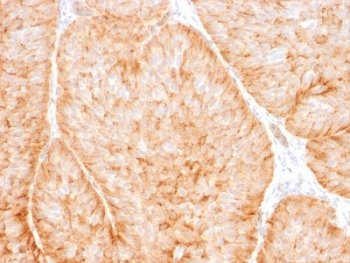

IHC staining of FFPE human esophagus tissue with SLC2A1 antibody (clone GLUT1/7308). Inset: PBS used in place of primary Ab (secondary Ab negative control). HIER: boil tissue sections in pH9 10 mM Tris with 1 mM EDTA for 20 min and allow to cool before testing.